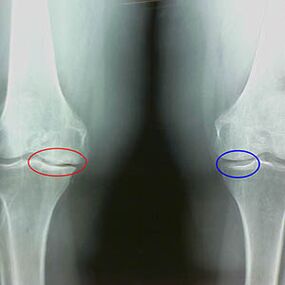

Caratteristiche X -raggi precoci della seconda fase dell'artrosi del ginocchio:

- i bordi appuntiti dei tubercoli inter -scrip sulla tibia, dove è attaccato il legamento a forma di croce;

- restringimento del divario articolare sul lato mediale;

- I bordi appuntiti dei condyli di ossa sui lati mediali, meno spesso in laterale, a seconda dello sviluppo della deformazione articolare Valgus o Varior.

Per la seconda fase di Larsen Il restringimento del divario articolare di oltre il 50% è caratteristico, ma questo può essere controllato solo in dinamica o confronto con un giunto diverso.